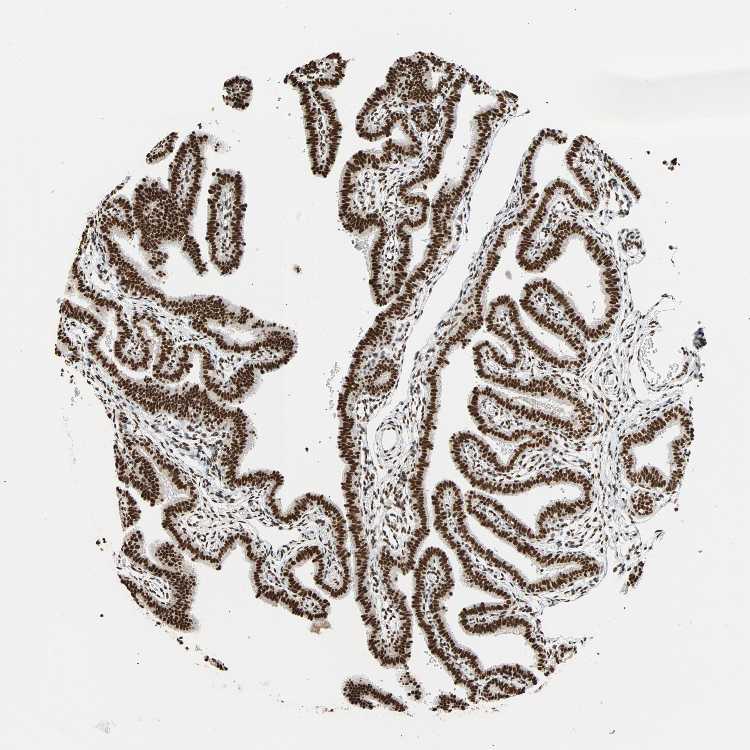

TISSUE PRIMARY DATA FALLOPIAN TUBE Show tissue menu

FALLOPIAN TUBE - Antibody stainingi

Antibody staining in the annotated cell types in the current human tissue is reported as not detected, low, medium, or high, based on conventional immunohistochemistry profiling in selected tissues. This score is based on the combination of the staining intensity and fraction of stained cells.

Each image is clickable and will lead to virtual microscopy that enables deeper exploration of all samples and also displays staining intensity scores, fraction scores and subcellular localization as well as patient and tissue information for each sample.

Antibody HPA007484

Glandular cells High